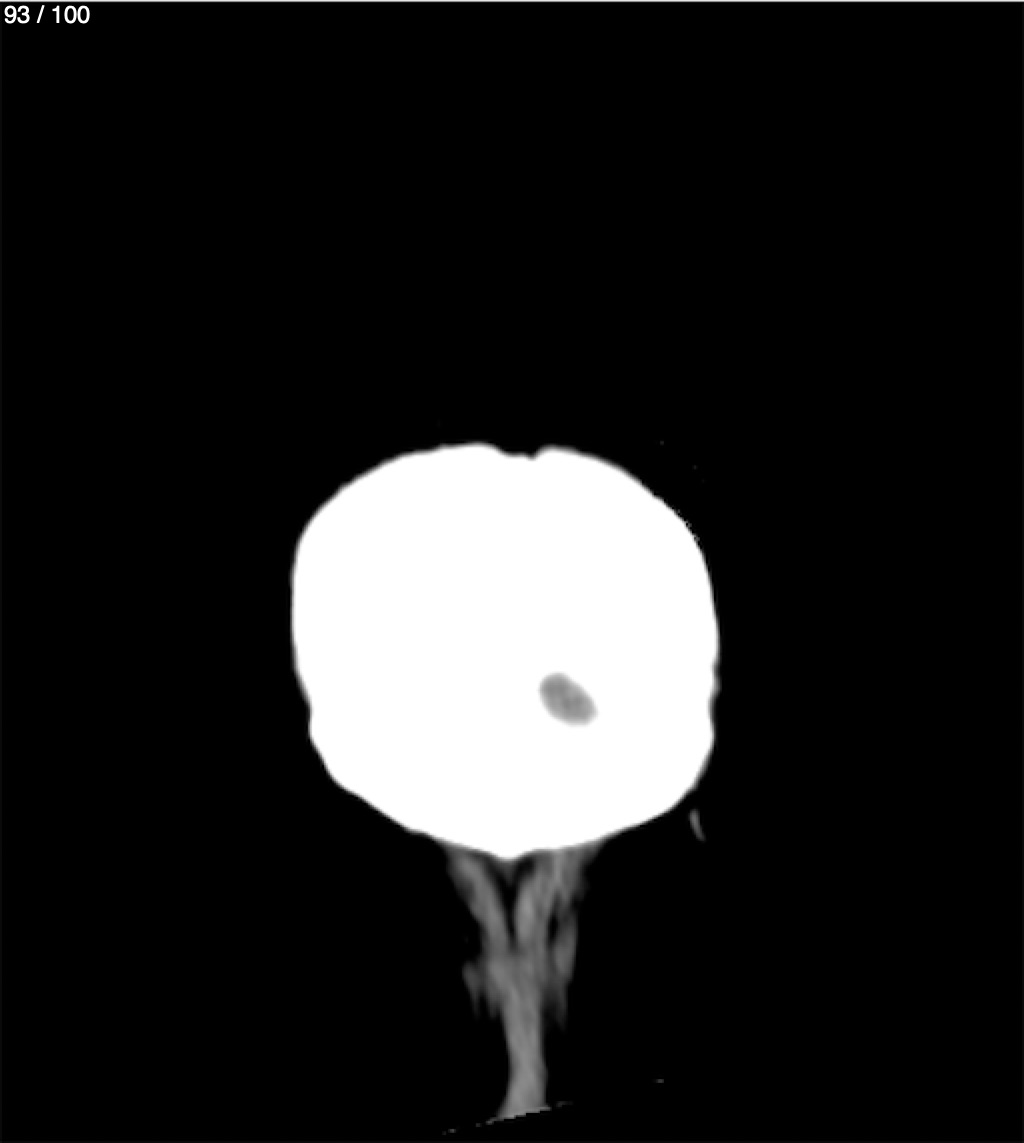

Jose Sosa Martinez 66A - Angiotac Craneo